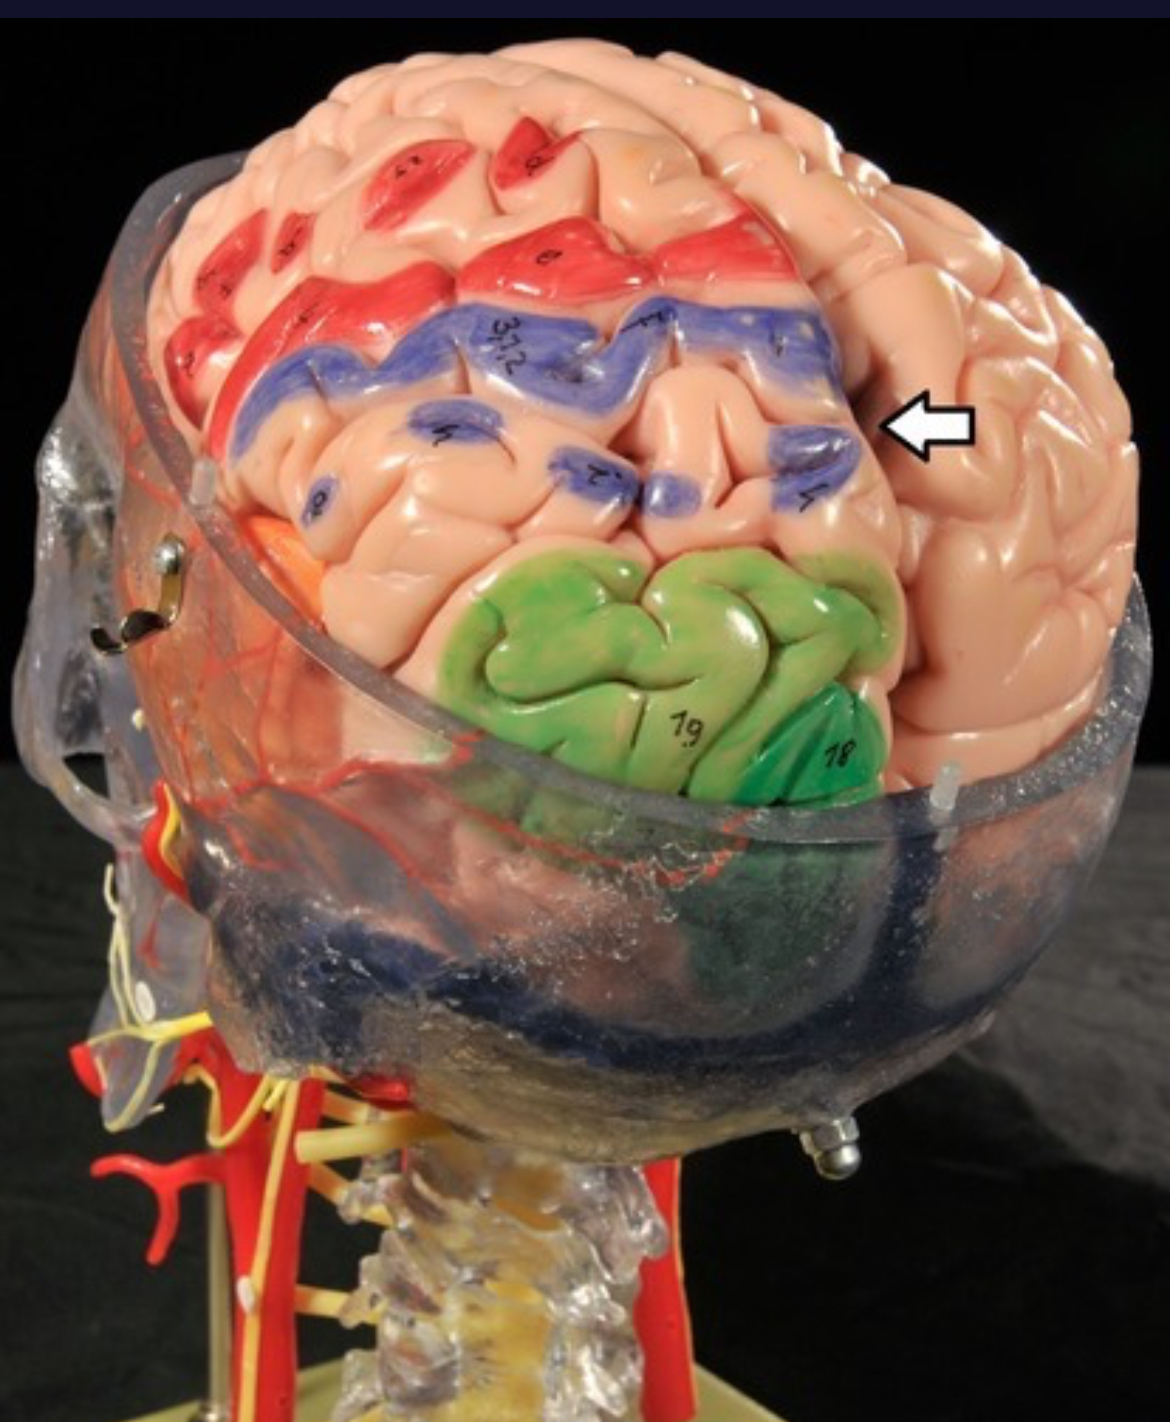

Cerebral cortex (gray matter)

Precentral gyrus

Postcentral gyrus

Central sulcus

Cerebellum